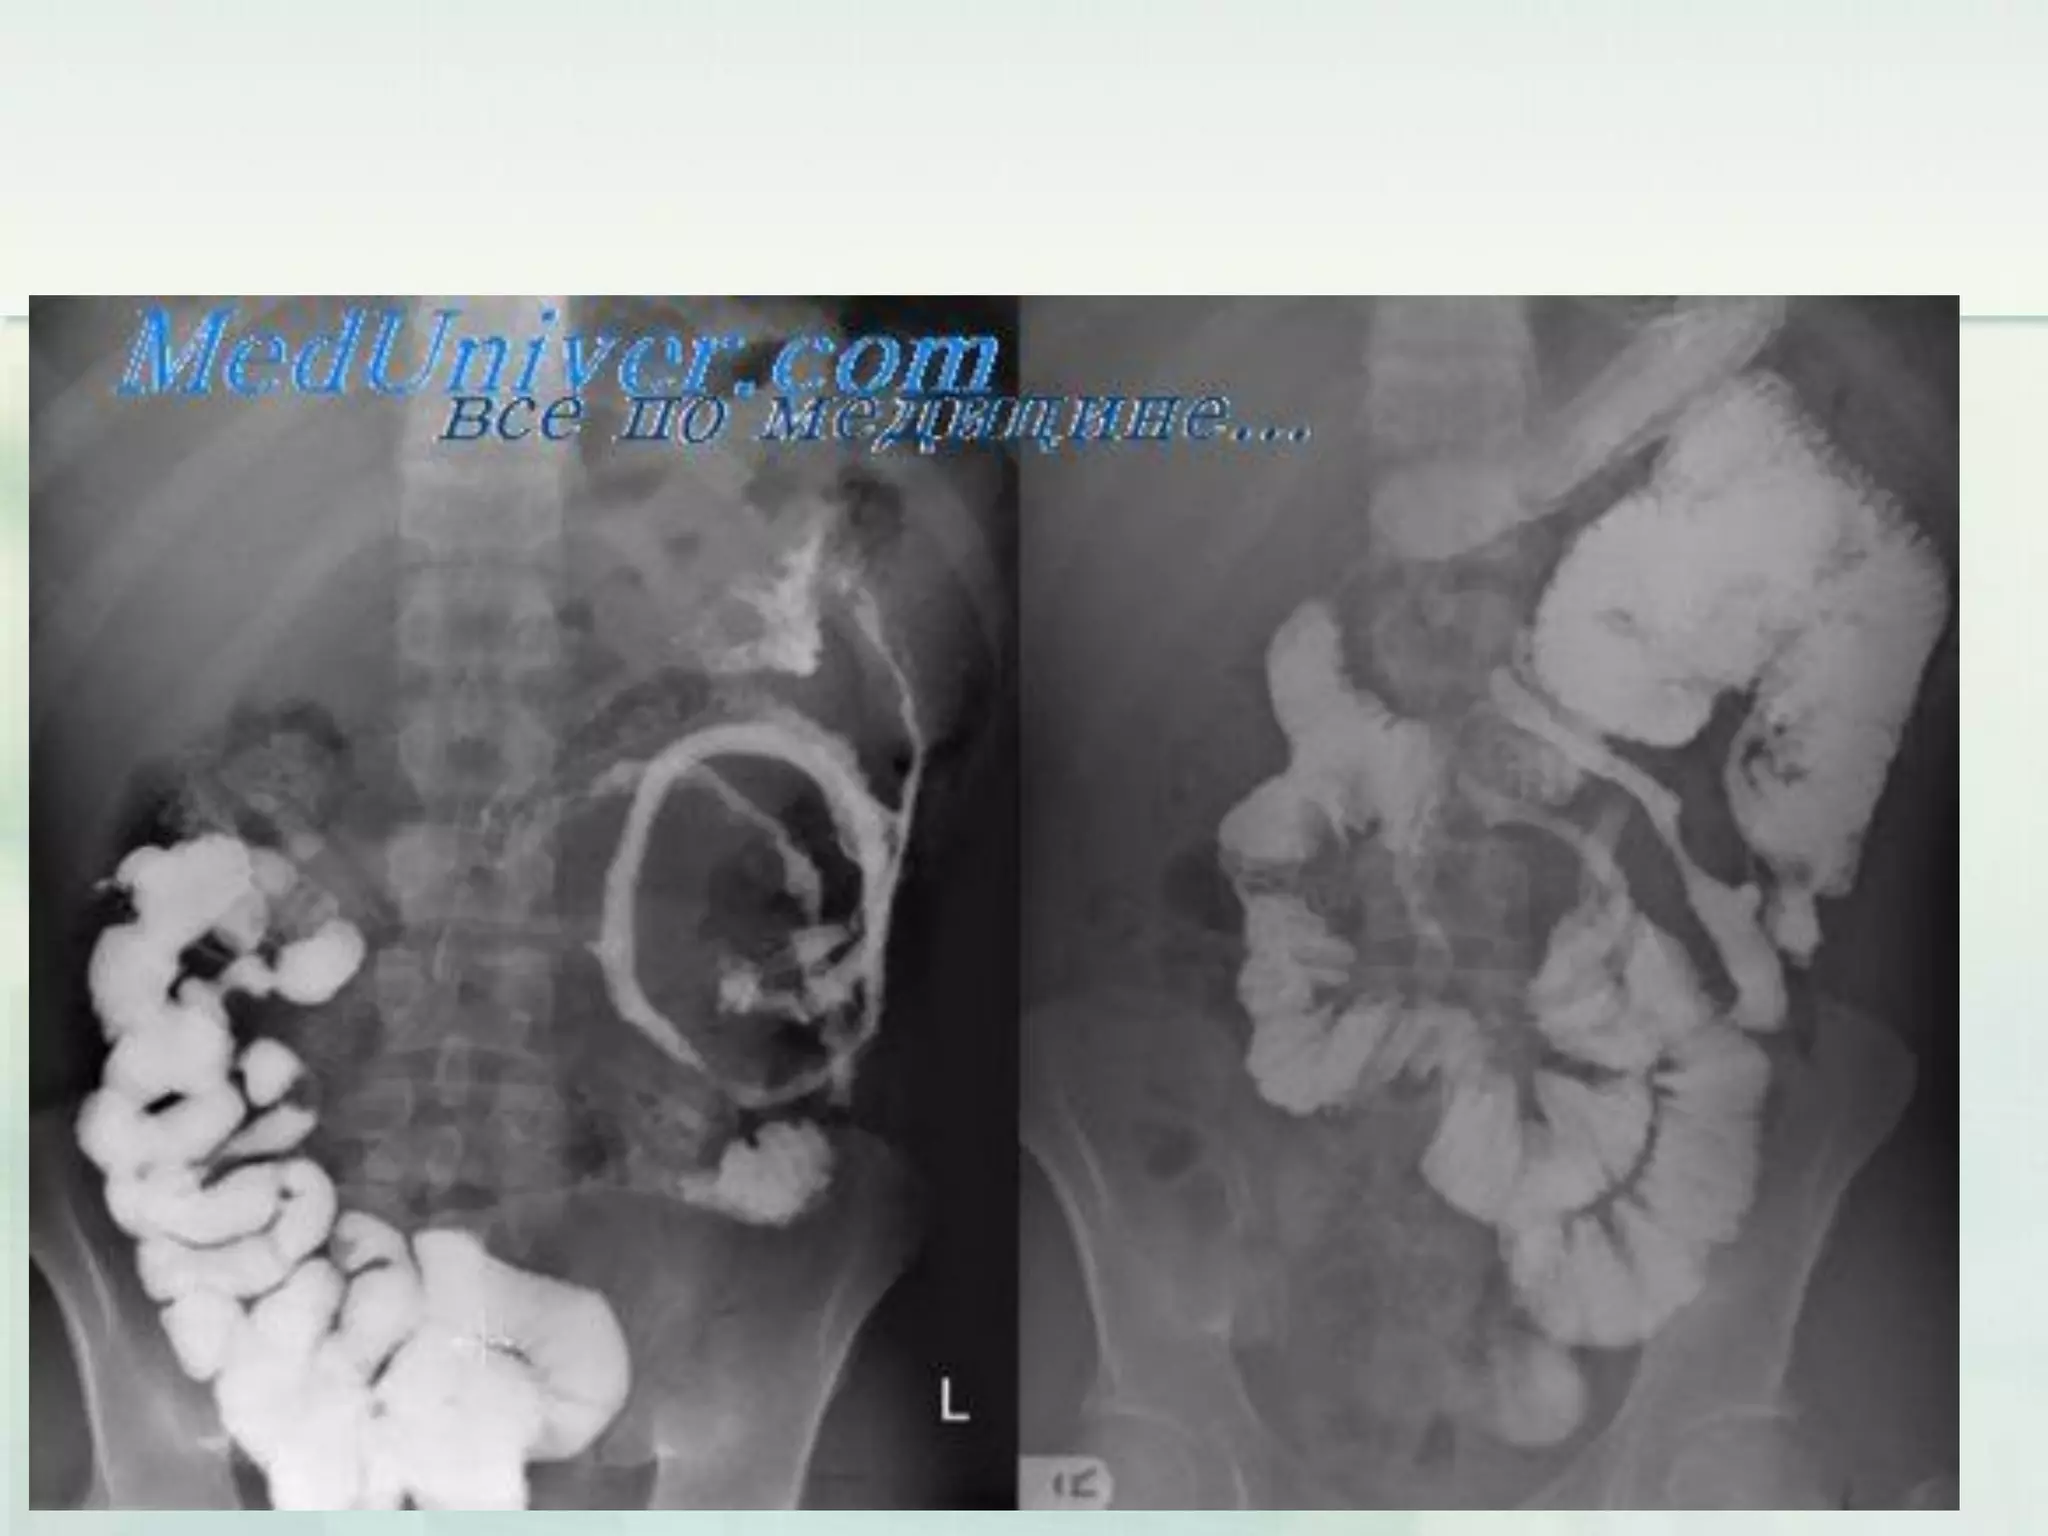

Laboratory investigations

(Large bowel obstruction)

 Abdominal films provide useful information:

they may suggest or confirm the diagnosis

and site of obstruction, and the degree of

cecal distension can be assessed from

them.

 The site of obstruction and its severity can

be detected with a retrograde contrast

study; the diagnosis of pseudo-obstruction

is also ruled out.

 Computed tomographic (CT) scans are of

value: they may illustrate the transitional

area of colonic obstruction, as well as

extracolonic abnormalities and more subtle

degrees of pneumoperitoneum.

Laboratory investigations (Large bowelobstruction)  Abdominal films provide useful information: they may suggest or confirm the diagnosis and site of obstruction, and the degree of cecal distension can be assessed from them.

Laboratory investigations (Large bowelobstruction)  The site of obstruction and its severity can be detected with a retrograde contrast study; the diagnosis of pseudo-obstruction is also ruled out.  Computed tomographic (CT) scans are of value: they may illustrate the transitional area of colonic obstruction, as well as extracolonic abnormalities and more subtle degrees of pneumoperitoneum.